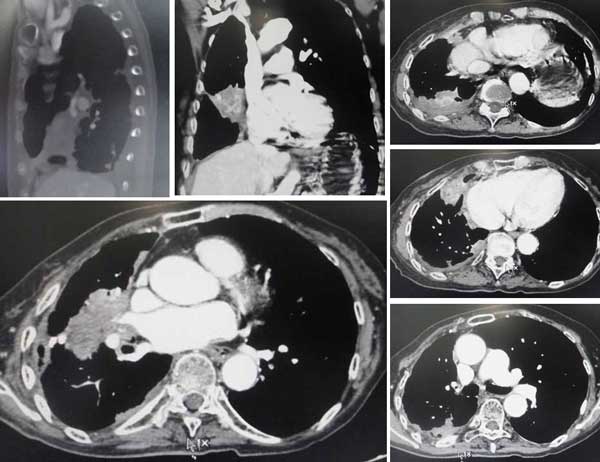

We went for the CT scan yesterday. We reached the hospital at 3 pm. Did the scan at 3.30 pm but only managed to see Prof X at 7.30 pm. Left the hospital at 8.30 pm. We ended up spending nearly 5 hours at the hospital.

CT scan 14 August 2012

Anyway, we are VERY HAPPY with the results. Mom was expecting the worst as she thought the cancer has spread to other areas hence the persistent and intense pain. But as it turns out, the cancer has not spread – still confined to the right lung only. The left lung is all clear.

When Prof X told us the results, Mom asked again in disbelief. “No spreading?” She was very happy. Prof X explained that the shape of the right lung has changed. The tumour has grown bigger and the pleura has thickened. There was some fluid but he said not to worry as its minimal. Prof X explained that due to the enlarged tumour and thickening of pleura, Mom will experience some chest congestion (which I think explains her shortness of breath?).

When we asked what is causing Mom’s pain then? Prof X explained that it’s from the enlarged tumour “pressing” the lining or thickening of the lining? (Hope I got this right.).